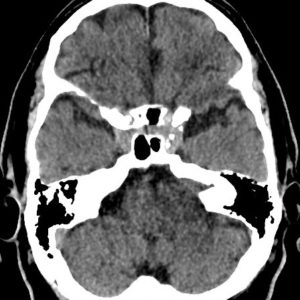

Chấn thương hàm mặt

Lượt xem: 275» 01-11-2018 -

Chấn thương hàm mặt

Lượt xem: 180» 01-11-2018 -